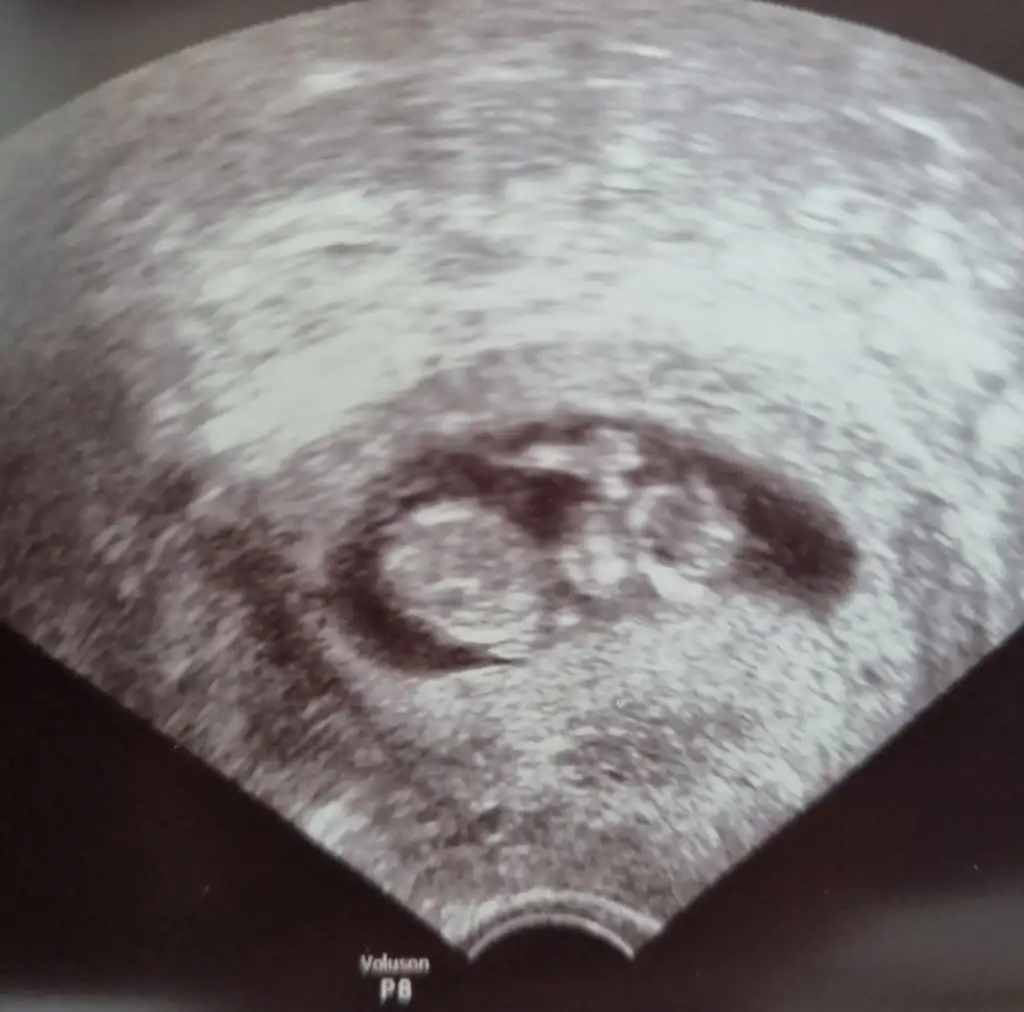

Net değil ama kız sanki başka USG varsa paylaşın 11 12 13 haftalar olmalıTahminlerinizi alabilirmiyim??? 12. Haftadan resim

Net değil ama kız sanki başka USG varsa paylaşın 11 12 13 haftalar olmalı

Yukari dogru cikanlar bacaklari degilmiNet değil ama kız sanki başka USG varsa paylaşın 11 12 13 haftalar olmalı

Ben size yazmıştım kız dedim diğer konudaBana ısrarla bakmadınız 12 hafta karından![]()

Ben size yazmıştım kız dedim diğer konuda